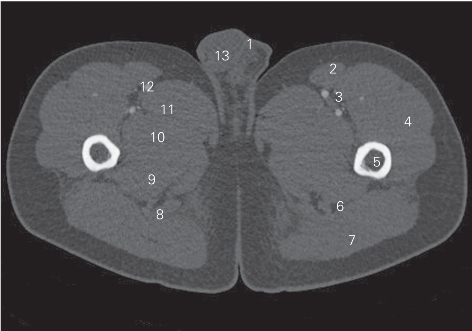

图5-7 经臀大肌下份的横断层CT图像(骨窗)

1 阴囊 scrotum 2 缝匠肌 sartorius

3 股静脉 femoral vein 4 股外侧肌 vastus lateralis

5 股骨 femur 6 坐骨神经 sciatic nerve

7 臀大肌 gluteus maximus 8 股二头肌长头 long head of biceps femoris

9 大收肌 adductor magnus 10 短收肌 adductor brevis

11 长收肌 adductor longus 12 股动脉 femoral artery

13 睾丸 testis